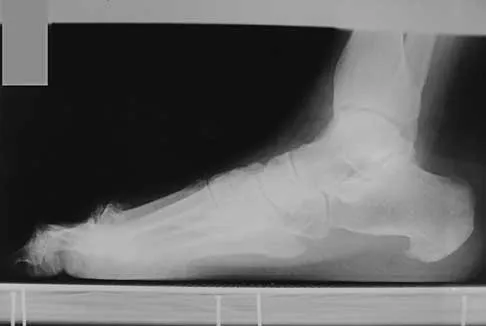

An obese 62-year-old man reports a 10-year history of progressive flatfoot deformity and a 3-month history of a painful callus along the plantar medial midfoot that has not improved with custom shoe wear, pedorthics, and callus care. There is no hindfoot motion, but functional ankle motion remains. He does not have diabetes mellitus. Radiographs are shown in Figures 27a and 27b. What is the best surgical option at this point?

Explanation

The deformity is long-standing, the hindfoot is immobile, and the radiographs reveal severe degenerative arthritis involving the entire hindfoot, severe deformity, and talonavicular dislocation. The "exostosis" responsible for the callus is the talar head; resection would severely destabilize the foot. Degenerative arthritis and fixed deformity preclude lateral column lengthening, medial slide calcaneal osteotomy, and talonavicular arthrodesis. Triple arthrodesis is the only viable option. Johnson JE, Yu JR: Arthrodesis techniques in the management of Stage II and III acquired adult flatfoot deformity. Instr Course Lect 2006;55:531-542.